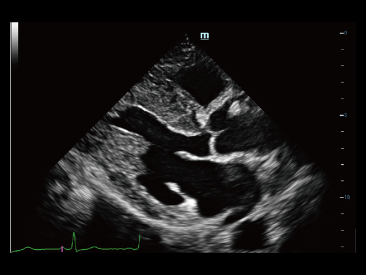

Sinds de oprichting van het bedrijf is Mindray voortdurend op zoek naar nieuwe manieren om het diagnostisch vertrouwen te vergroten. Resona 7 wordt aangestuurd door de meest revolutionaire ZONE Sonography?-technologie. Zijn nieuwe ZST+-tilt de kwaliteit van ultrasoundbeeldvorming naar een hoger niveau door middel van zoneacquisitie en kanaalgegevensverwerking.

Naast de hoogwaardige beeldvormingskwaliteit verbetert de Resona 7 tevens de klinische onderzoeksmogelijkheden met de revolutionaire V Flow voor vasculaire hemodynamische evaluatie, en de intelligentste vlakacquisitie van een 3D-gegevenssets voor de diagnose van het foetale, centrale zenuwstelsel. Met zijn combinatie van de meest intu?tieve, op vingerbewegingen gebaseerde multi-aanrakingsbediening en alle essenti?le klinische functies loopt de Resona 7 voorop in de nieuwe golven van ultrasoundinnovatie.